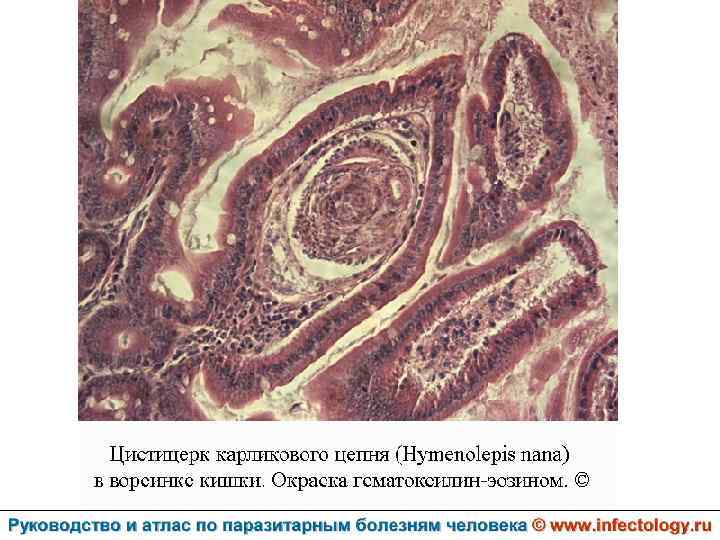

Гименолепидоз (шифр по МКБ 10 – B 71. 0) – контагиозный гельминтоз человека и некоторых мышевидных грызунов, характеризующийся, главным образом, нарушениями функций пищеварительного тракта.